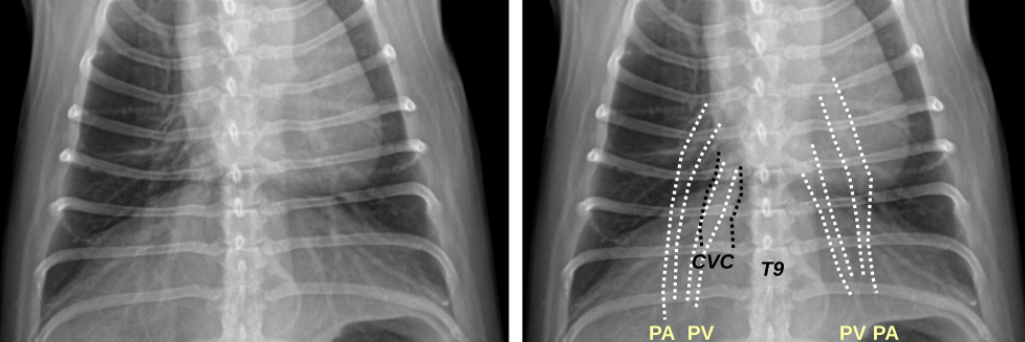

1. Normal Anatomy

| Thorax | |